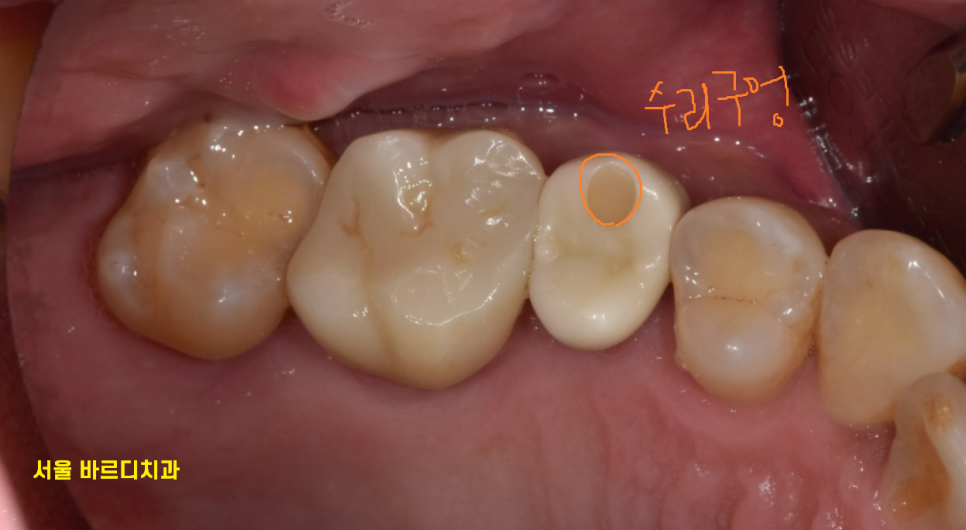

240126

동그라미 구멍이 있는 치아가

풍산동 임플란트 한 부위입니다.

구멍이 있는 것은 추후 임플란트에 문제가 생겼을 때

수리하기위함인데

다음 포스팅에서 설명드리겠습니다.